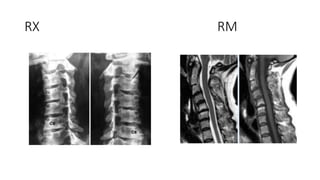

DIAGNOSTICO

RX RM